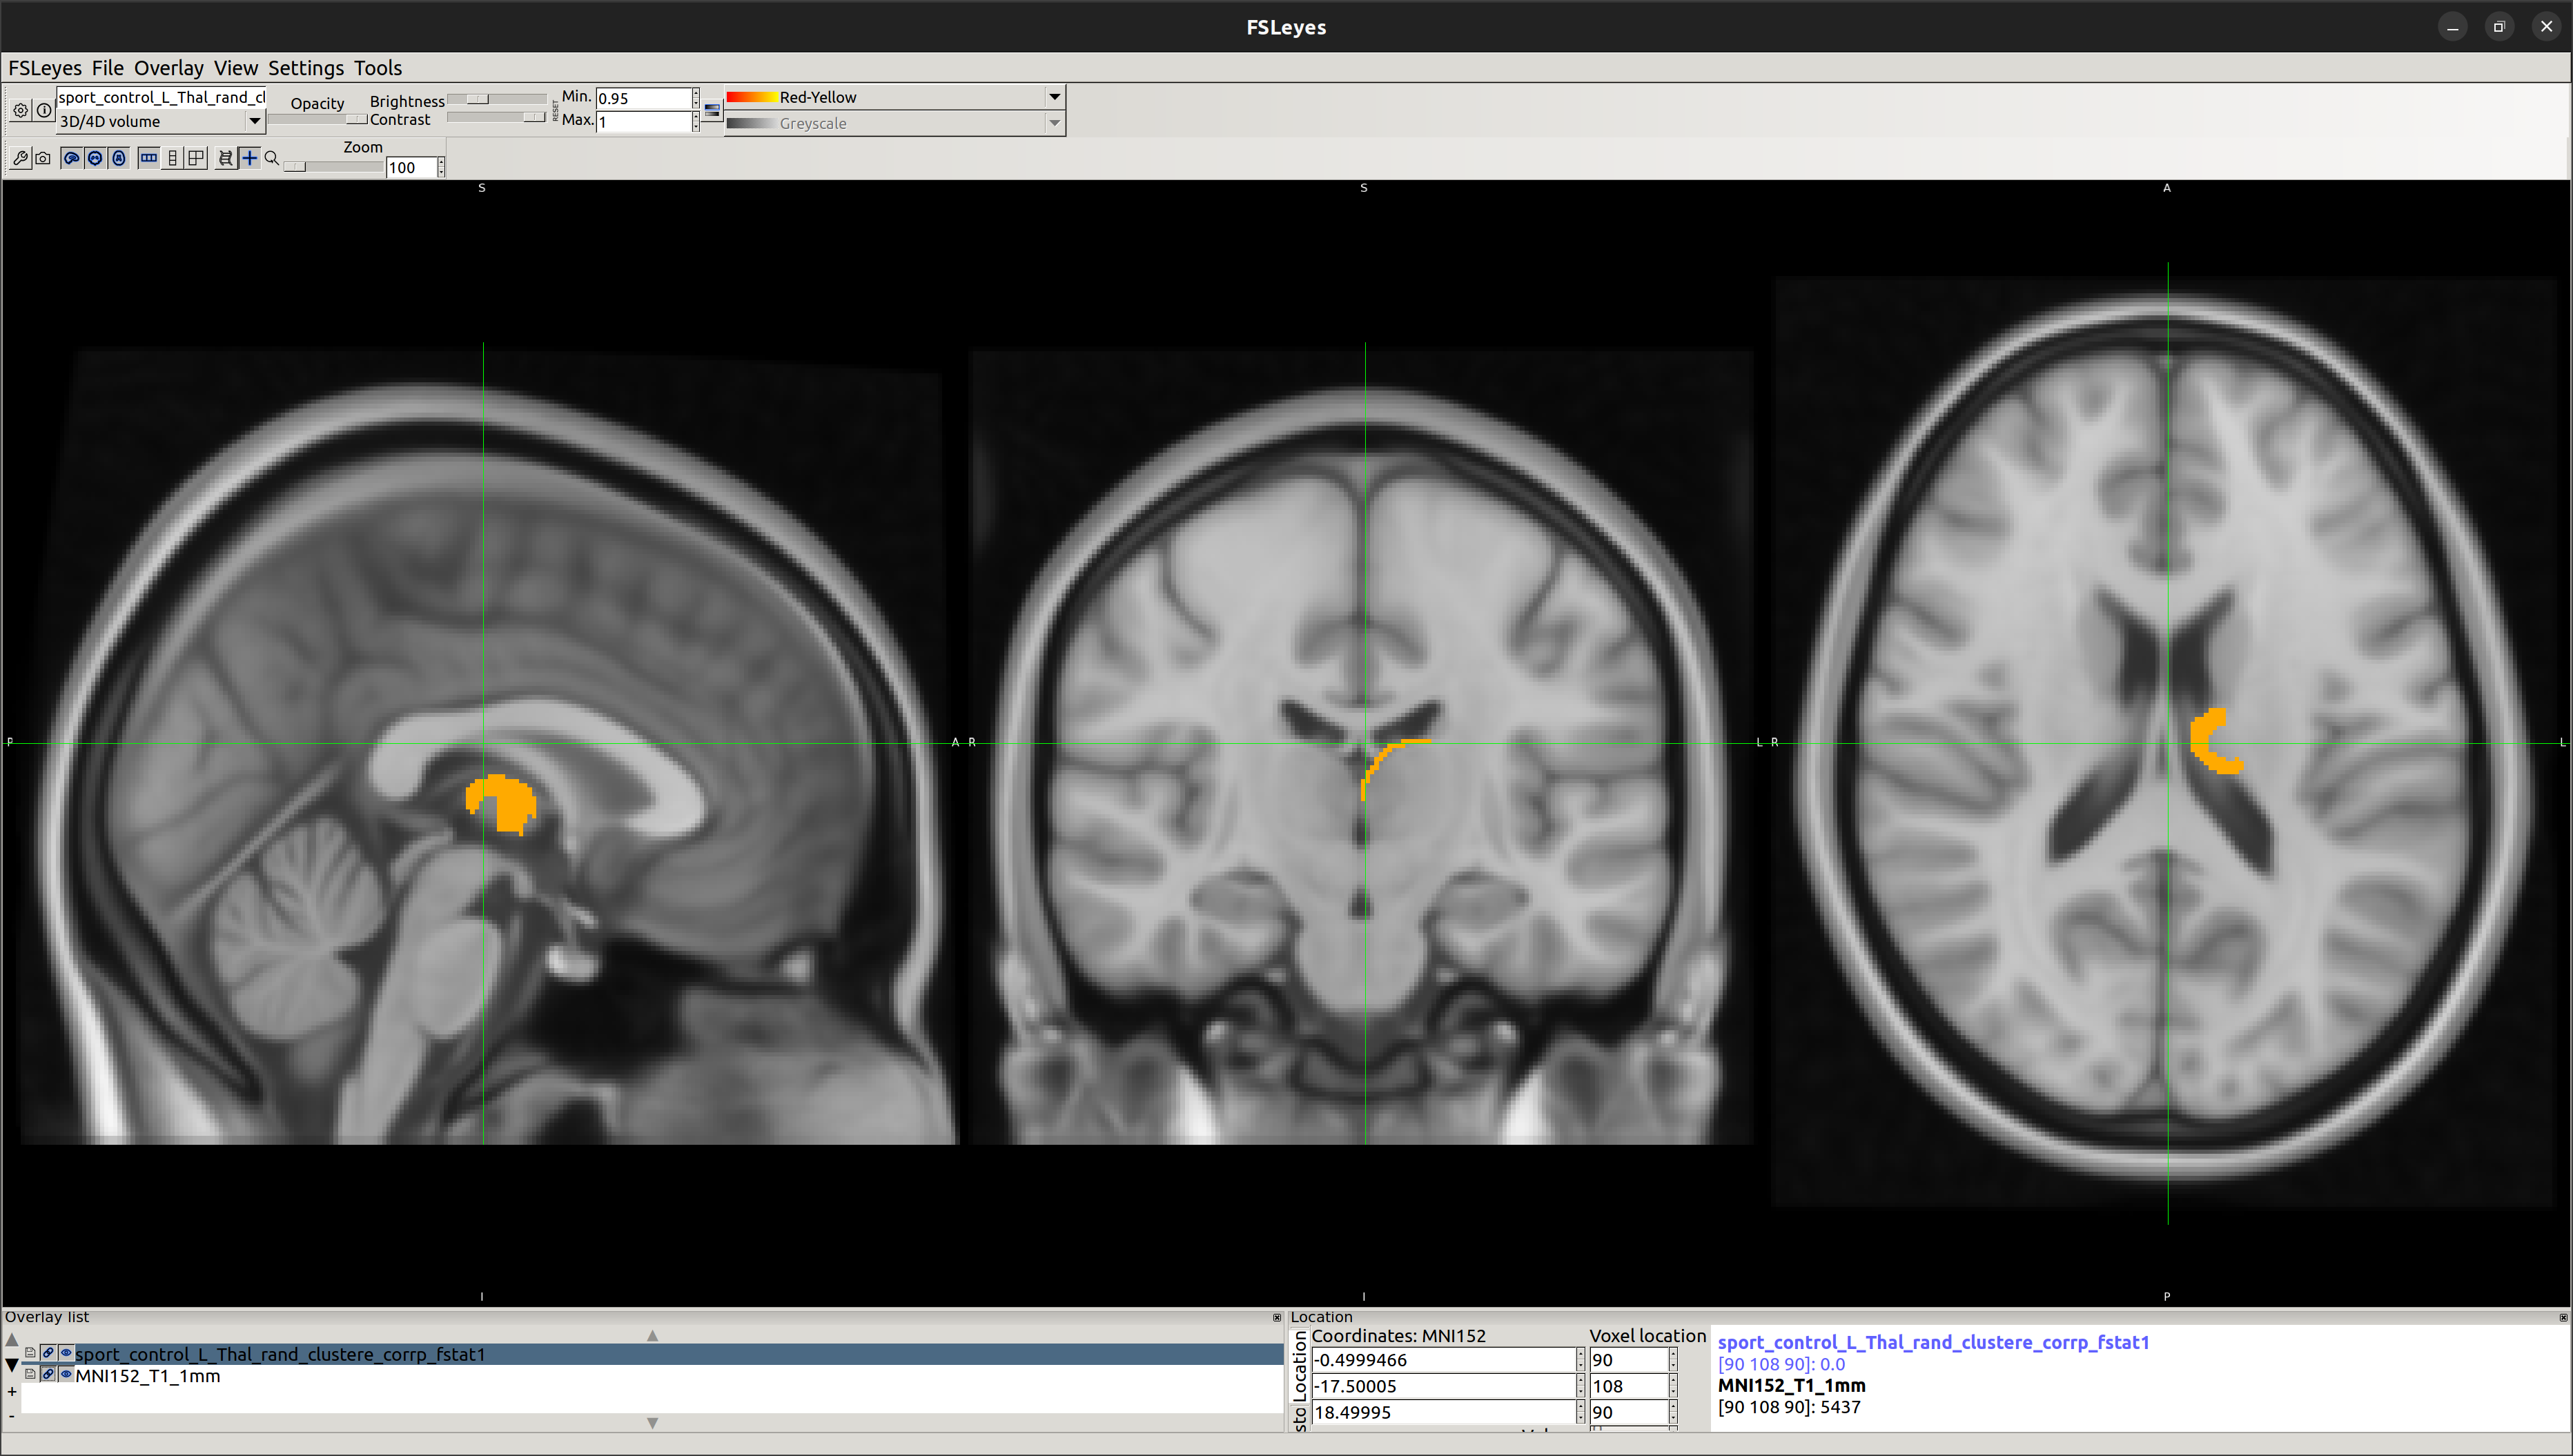

Automated segmentation of subcortical structures in the brain has been completed using FSL FIRST [a model-based segmentation/registration tool] tool.

Using this vertex analysis, marked differences in shape have been found in the two following areas:

[1] Left-Putamen

[2] Left-Thalamus